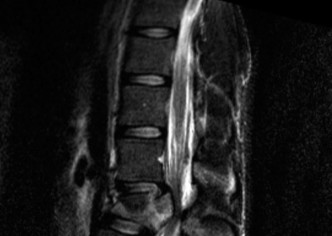

To definitively assess the integrity of the soft tissue stabilizers and the neural elements, a Magnetic Resonance Imaging (MRI) scan without contrast was performed. Historically, textbooks propagated the "50-50-25 rule," suggesting that a burst fracture was inherently unstable if it exhibited >50% canal compromise, >50% loss of vertebral body height, or >25 degrees of kyphosis. Modern spine trauma surgery has largely debunked this rigid radiographic dogma. We now understand that these bony metrics alone do not dictate mechanical instability. The true arbiter of stability is the Posterior Ligamentous Complex (PLC).

The MRI, particularly the Short Tau Inversion Recovery (STIR) and T2-weighted sagittal sequences, provided the definitive diagnosis. The images demonstrated profound hyperintensity and discontinuity of the ligamentum flavum, the interspinous ligaments, and the supraspinous ligaments at the T12-L1 level. The facet joint capsules were also disrupted, indicated by fluid within the joints. This complete failure of the PLC means the posterior tension band is gone. Regardless of the bony parameters, this spine cannot resist physiological flexion loads. If treated non-operatively, this injury will inevitably lead to progressive kyphosis, delayed neurological deficit, and intractable pain.